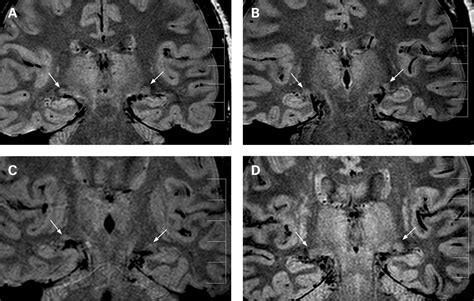

Moreover, advancements in neuroimaging, such as high-resolution fMRI, are allowing researchers to visualize the activity within the individual layers of the LGN in living humans. This technology provides unprecedented insight into how visual processing is affected by neurodegenerative diseases and helps map the pathways involved in visual processing disorders.

• lateral geniculate nucleus mri